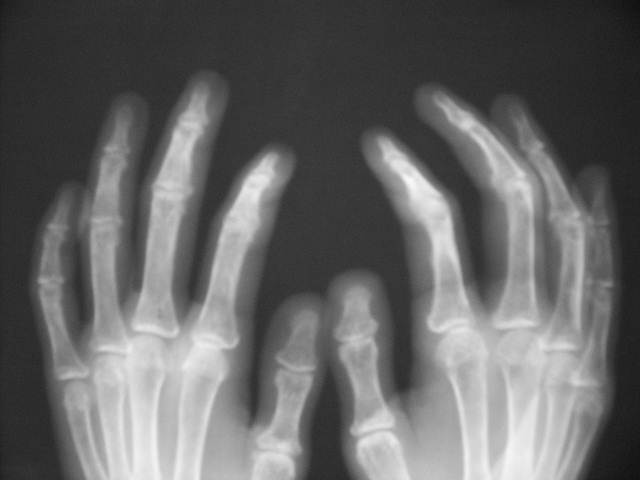

PSORIATRIC ARTHRITIS1